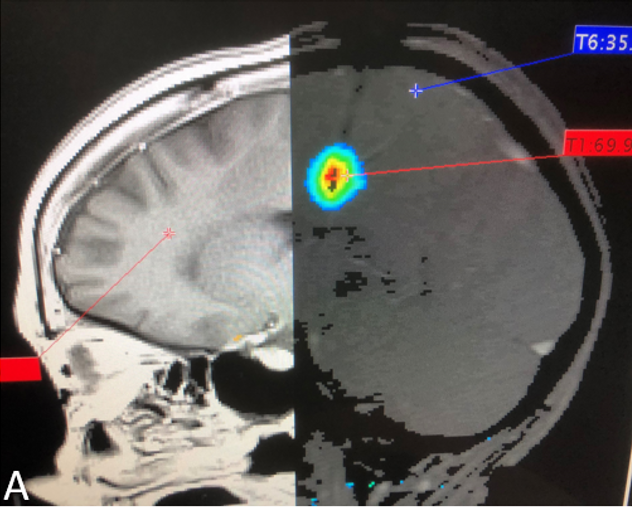

[144]. J. Blackwell, M.J. Krasny, A. O'Brien, K. Ashkan, J. Galligan, M. Destrade, N. Colgan.

Proton resonance frequency shift thermometry: A review of modern clinical practices.

Journal of Magnetic Resonance Imaging,

(2020) to appear.

Publisher | pdf